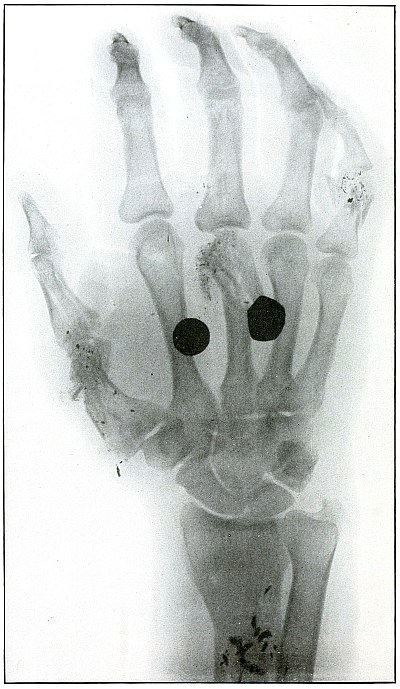

Plate 43.

_

[Pg 97]

Rifle—Plate 43.

UPPER EXTREMITY.

Gunshot Fracture of the Metacarpus.

Wound of entrance, inner aspect of the hand over proximal end of the fifth metacarpal.

Wound of exit, on the outer border of the hand over the distal end of the second metacarpal.

The velocity of the bullet was in mid or long range, as it displaced no fragments, and as it made a point of entrance and exit about the same in appearance.

The wound was infected, which is more frequently the case in the hand than in the forearm.

The treatment is conservative with free incision and drainage in the management of infection. [Pg 98]